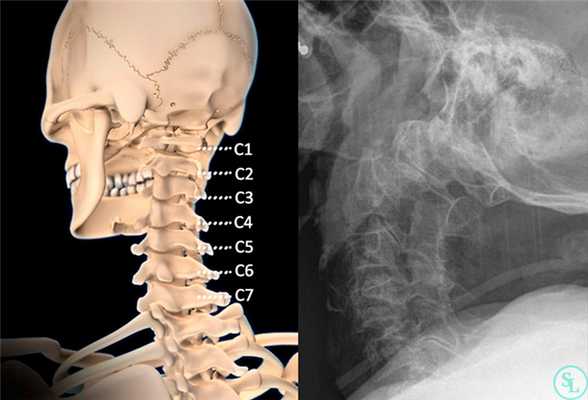

Шейный отдел позвоночника состоит из семи позвонков и шести межпозвонковых дисков. Между головой и первым шейным позвонком диска нет. Между первым и вторым позвонками тоже нет диска. Диски начинаются только между вторым и третьим позвонками. Счёт позвонков и дисков идёт от головы. Позвонки в шее обозначаются латинской буквой «C», от латинского слова «Cervix» — шея и цифрой порядкового номера от 1 до 7 — C1, C2, C3, C4, C5, C6, C7. Диски обозначаются по-другому. Чёрточка как бы, указывает между какими позвонками расположен диск: C2-C3, C3-C4, C4-C5, C5-C6, C6-C7, C7-Th1. «Th» означает «Thorax» — грудь. В зависимости от того какой диск поражён, в какую сторону выпячивается грыжа — назад или в бок и от того, воздействует ли она на позвоночные артерии, спинной мозг или на нервы, будут зависеть симптомы грыжи диска шейного отдела.

Шейный отдел образован 7-ю позвонками, но в отличие от других отделов позвоночника, межпозвонковые диски располагаются не между всеми. Их в шейном отделе только 5. Первые 2 позвонка (атлант и аксис) не имеют между собой хрящевой прослойки. Поэтому грыжи могут формироваться в дисках от С2 до С7, но в подавляющем большинстве случаев диагностируются грыжи С5—С6 и С6—С7.